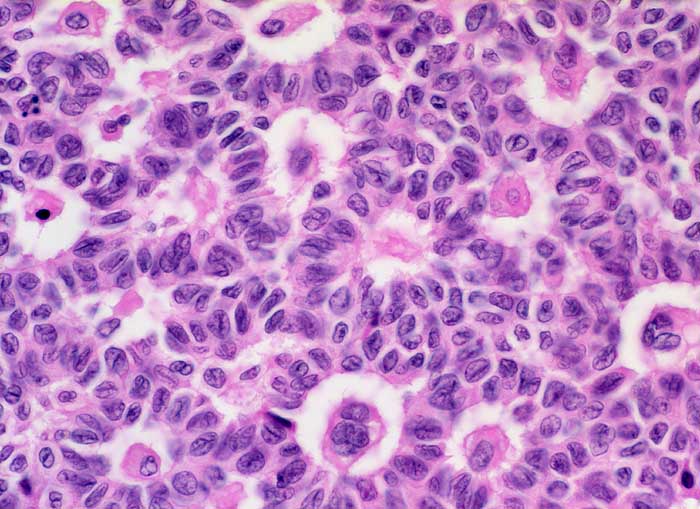

Granulosazelltumor des Ovars

maligner Tumor

Ovar

Morphologie